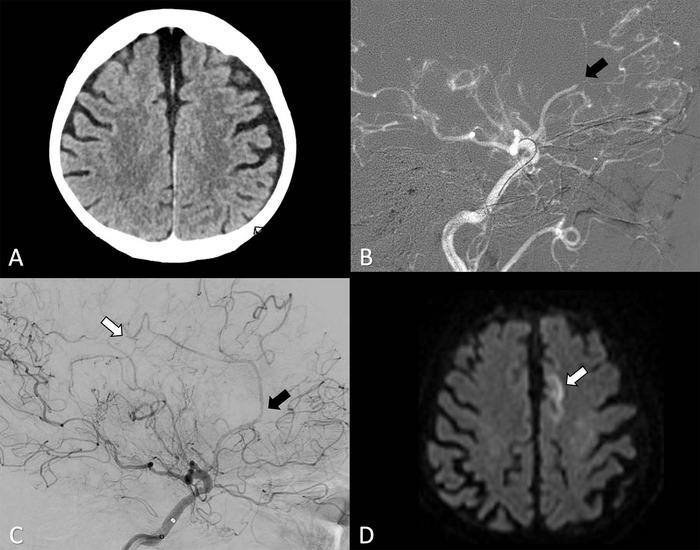

Thrombectomy is commonly performed to remove blood clots from brain arteries. It is often done to treat strokes arising from blood clots in the larger arteries that supply blood to the brain. When done promptly, thrombectomy can sometimes be more successful than clot-busting drugs in mitigating long-term damage to the brain.

Recent advances in technology have made it possible to perform thrombectomy in some of the narrower vessels in the head—vessels like the anterior cerebral arteries that arise from the internal carotid artery. However, evidence supporting a potential benefit of thrombectomy for these vessels remains unknown.

As part of the Treatment fOr Primary Medium vessel Occlusion Stroke, or TOPMOST trial, researchers in Germany compared thrombectomy with medical treatment in 154 patients. The patients all had primary isolated anterior cerebral artery medium vessel occlusions, or obstructions. The patients underwent thrombectomy or best medical treatment, which typically involves medications to dissolve the clot and reduce blood pressure. In some cases, patients may receive intravenous thrombolysis, the introduction of clot-busting drugs to the bloodstream or directly to the site of clot.

The results showed that thrombectomy was a safe and technically feasible option. Within the first 24 hours after treatment, thrombectomy patients had similar outcomes to those who received best medical treatment alone with or without intravenous thrombolysis. Longer term, both groups had similar clinical and functional outcomes. Mortality rates were similar in both groups.